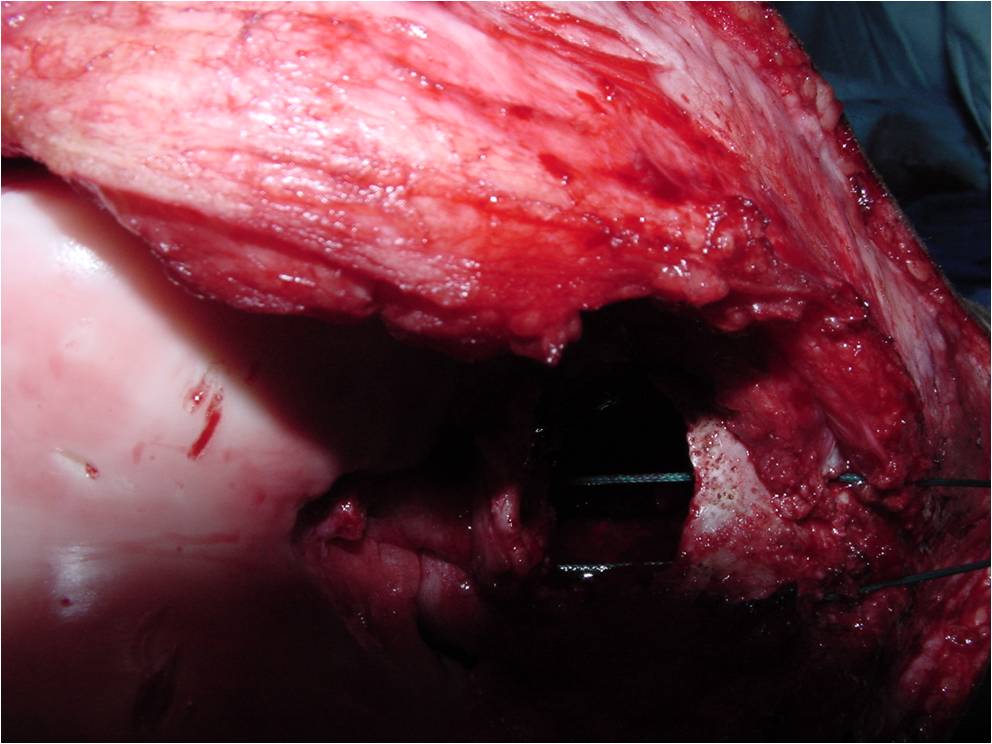

General Information Enchondroma is a benign indolent intramedullary hyaline cartilage neoplasm Accounts for 10% of all benign osseous tumors Limited growth, most lesions are less than 5 cm in maximal dimension Bones grow from a cartilaginous growth plate that...